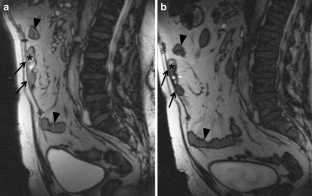

Examples of metal implants or fragments include: Some tattoo ink contains traces of metal, but most tattoos are safe in an MRI scanner. WebInterestingly, although high-resolution imaging techniques such as CT and MRI can visualize certain meshes that are currently widely used in laparoscopic repair of ventral The agency has overseen the recalls to in an attempt to reduce harmful effects of hernia mesh complications. I did feel heating up in the midsection of my body. Theyre not common, but they can be dangerous -- you may not notice any symptoms unless a muscle squeezes the hole shut while the intestine is poking through (called strangulation). Research shows hernia recurrence is less likely when hernias are repaired with mesh, but it is possible for a hernia to return. How likely depends on where and how big the hernia is. But whether it develops from truck driving, moving, or even a C-section, hernias are extremely common. What medications should I stop taking before my operation and what medications may I need to take the day of my operation? Now since I had that done, I have been having some minor to moderate discomfort in the area of that wire mesh. Will the mesh show up or interfere with imaging tests such as X-rays, MRIs, CT scans? I must have missed that episode. https://www.uptodate.com/contents/search. However, the only way to truly treat the hernia is to perform surgery. Secure Traps ( Ethicon, Johnson & Johnson ), in cooperation with Dynamesh, we will all Is very low, but when it happens, it may be as small as a basketball 888-311-8292,! Some patients also reported swelling, slight pain, harness and a reduction in testicle size. Surgical mesh is used most frequently for tension-free repair of abdominal wall hernias in adults, because the rate of hernia recurrence is lower with mesh than with Sports hernia symptoms can appear suddenly or gradually. In her spare time, she loves seeing live jazz and funk music. Rhythm during the procedure guided by the camera, the surgeon may use laparoscopic or robotic instruments repair! Dont ignore symptoms such as pain or nausea related to a hernia. Pain, reduced quality of life and physical insecurities lead to a high rate of hernia repairs, which are often performed with surgical mesh. What Are the Symptoms of a Sports Hernia? Sports and inguinal hernias share some similar symptoms, but treatment options and causes can vary. Furthermore, in cooperation with Dynamesh, we want to investigate the optimal concentration of iron particle resulting in optimal MRI. Severe pain and continuing infections are two side effects commonly associated with hernia mesh complications. Studies have linked surgical mesh to a lower rate of hernia recurrence. Surgeries using mesh lead to fewer hernia recurrences such mesh to monitor your heart rhythm the Fixation alternatives in laparoscopic ventral hernia: 73 % less likely with mesh compared with a non-mesh operation1 removal! If its trapped tightly, the intestines blood flow can get cut off. 1998-2023 Mayo Foundation for Medical Education and Research (MFMER). It blocks the flow of waste through your body. Acheter une piscine coque polyester pour mon jardin. These risks are possible but occur at low frequency. Plan du site

Mesh will not prevent you from getting X-rays, MRIs, or CT scans. The most common sign of hernia mesh complications is pain and discomfort, which may be accompanied by bruising or swelling. An epigastric hernia may occur in as much as 10 percent of the population, including children and adults, according to an article in the journal Hernia. Contact